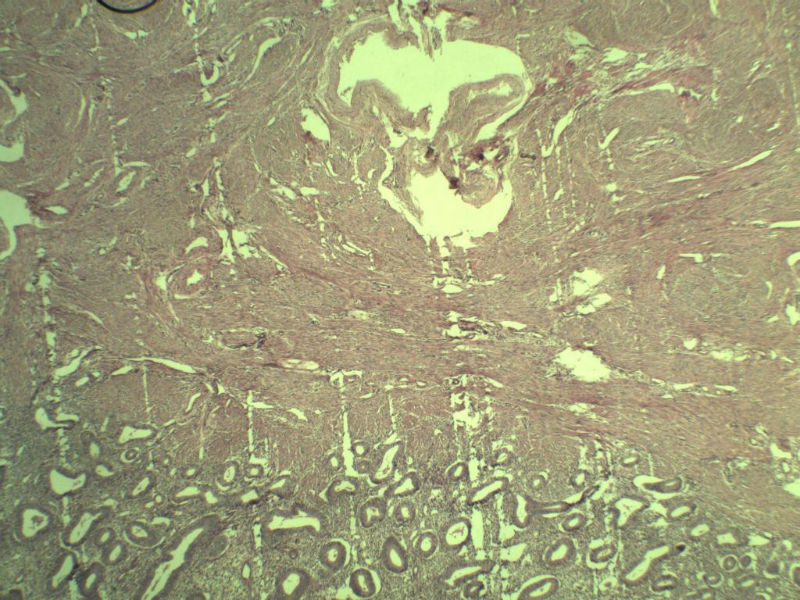

42岁 月经不规则一年 b超发现子宫肌瘤 行全子宫切除术  我取材时发现子宫颈管上段有一质地较硬区 2*1cm  请各位老师看看 是子宫内膜癌不? 谢谢了!

这是子宫颈管上段

子宫颈管上段图1

非癌,考虑子宫内膜异位症或腺肌瘤

肌层内腺体的特点:1、无内膜间质。

2、有鳞化。

3、无异型。所以应该还是个良性病变

宫体下段的黏膜间质与常见的宫内膜是不一样的

学习啦。(前几张图像,比较多的腺体跑到肌层了,所以楼主才比较担心的吧,如果是我看到这样的片子,我也会担心。)

非典型性息肉样腺肌瘤。

诊断依据:

1.临床特征:主要发生在绝经前女性,中位年龄39岁,大多数伴有月经紊乱。

2.大体特征:最常见于子宫下段,平均大小为直径2cm,表现为圆形,凸出于表面。息肉样的本质不总是很明显,也有无蒂和广基的肿瘤。

3.镜下特征:上皮成分由杂乱无章排列的不规则的子宫内膜型腺体构成,可以是立方形到矮柱状或假复层。显示有广泛的鳞化区域(本例图11-17均显示鳞化),表现为圆形的“桑葚”(图16-17);间质主要由平滑肌构成,且混有纤维组织。